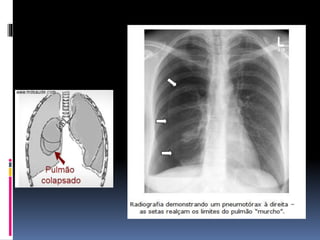

PNEUMOTÓRAX

 FISIOPATOLOGIA: traumático, primário ou

secundário (DPOC, asma, fibrose cística,TB,

etc...)

 Ruptura de folheto

 Perda da pressão

negativa intrapleural

 Colapso pulmonar

 Mecanismo de

Válvula

 Processo progressivo

 F.R.: tabagismo, pneumotórax prévio, DPOC,

mudanças barométricas agudas.

 Grupo de risco elevado: jovens e longilíneos

(para pneumotórax espontâneo)

 Q.C.: dor pleurítica e dispnéia de início súbito

(que pode ser decorrente da dor ou de

comprometimento da oxigenação em casos

mais graves.

 E.F.:

 Dispnéia e cianose

 Taquipnéia, taquicardia, hipotensão,

sudorese

 ↓ MV eTimpanismo à percussão pulmonar

 ↓ expansibilidade e FTV

 No pneumotoráx hipertensivo pode haver

desvio de traquéia (para lado contrário da

lesão) e estase jugular